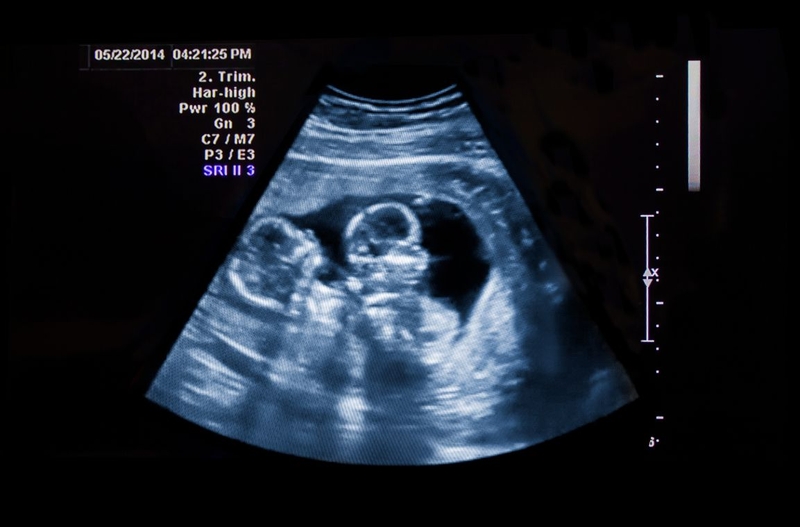

Theo thống kê, cả thai phụ, thai nhi và trẻ song thai đều có nguy cơ gặp rủi ro về sức khỏe cao hơn nhiều lần so với trường hợp đơn thai. Đây là lý do trong suốt thai kỳ, bà mẹ mang thai đôi cần quan tâm đến việc siêu âm song thai.

Siêu âm là một kỹ thuật hữu ích trong việc theo dõi và quản lý thai kỳ nói chung và thai kỳ song thai nói riêng. Siêu âm song thai giúp bác sĩ và thai phụ dễ dàng theo dõi, chăm sóc song thai từ chẩn đoán ban đầu đến khi sinh. Trong phạm vi bài viết này, Long Châu sẽ cùng bạn tìm hiểu lợi ích của siêu âm thai đôi và quy trình siêu âm thai đôi.

Song thai hay mang thai đôi là tình trạng có 2 thai nhi cùng một lúc hình thành và lớn lên trong tử cung của người mẹ. Song thai thường được chẩn đoán bằng hình ảnh siêu âm thai đôi. Đây là phương pháp khám cận lâm sàng được sử dụng phổ biến nhất, thường xuyên nhất trong mọi trường hợp mang thai.